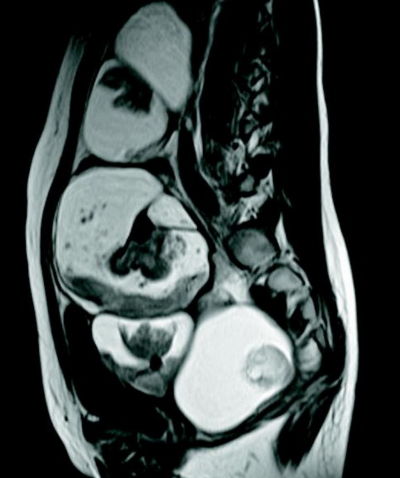

血液所見:赤血球380万、Hb 10.1g/dL、Ht 32%、白血球4,000、血小板19万。血液生化学所見:総蛋白7.0g/dL、AST 22U/L、ALT 20U/L、LD 190U/L(基準120〜245)、α-フェトプロテイン〈AFP〉5ng/mL(基準20以下)、CA19-9 35U/mL(基準37以下)、CA125 30U/mL(基準35以下)。下腹部MRIのT2強調像、T1強調像及び脂肪抑制T1強調像を別に示す。

T2強調像

T1強調像

脂肪抑制T1強調像